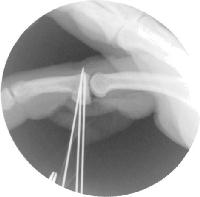

Here, the graft has been harvested and sculpted to fit the remaining joint. Three 0.035" K wires are in place for provisional fixation.

Intraoperative fluoroscopy confirms proper realignment of the joint with the bone graft in place.

The pins are replaced with screws, one at a time. Here, two 1.3mm and one 1.0mm screws were used.